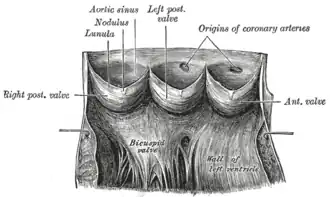

The aortic valve normally has three cusps however there is some discrepancy in their naming.[2] They may be called the left coronary, right coronary and non-coronary cusp.[2] Some sources also advocate they be named as a left, right and posterior cusp.[3][4] Anatomists have traditionally named them the left posterior (origin of left coronary), anterior (origin of the right coronary) and right posterior.[2]

The three cusps, when the valve is closed, contain a sinus called an aortic sinus or sinus of Valsalva. In two of these cusps, the origin of the coronary arteries are found. The width of the sinuses in cross-section is wider than the left ventricular outflow tract as well as wider than the ascending aorta. The junction of the sinuses with the aorta is called the sinotubular junction. The aortic valve is located posterior to the pulmonary valve and the commissure where the anterior two cusps join together points toward the pulmonary valve. It is these two sinuses that contain the origin of the coronary arteries. In the congenital disease known as transposition of the great arteries, these two valves are reversed (the anterior valve is the aortic valve) and the origin of the coronaries still follows this "rule" that the origins are in the sinuses facing the pulmonary valve.

The term "semilunar" refers to an approximate half-moon shape of the valve leaflets.[5]